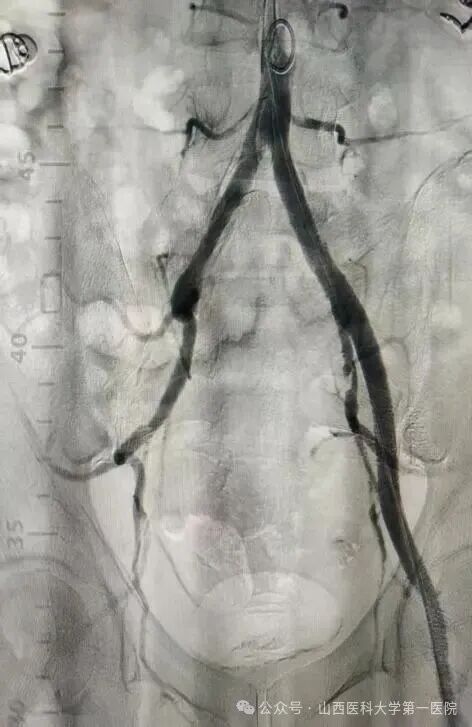

52岁王先生有长期高血压、糖尿病史,且未规范治疗控制,长期吸烟饮酒,饮酒量每日1斤左右,近年来逐渐出现间歇性跛行症状。10月20日凌晨,王先生突发右下肢发冷疼痛,当地医院下肢血管超声提示右侧髂动脉、股总动脉、腘动脉闭塞,紧急转诊至山医大一院血管外科。入院时患者右足发绀、皮温差,右足运动感觉明显减退,患侧股动脉、腘动脉、胫后动脉、足背动脉均无法触及搏动,这种急性髂股动脉血栓形成病情十分危急,死亡率40%以上,随时面临截肢与生命危险。

患者的全身状况同样堪忧,心肝肾功能异常,感染指标显著升高,“必须立刻打通血管,同时兼顾全身多器官的保护,既要保命,更要尽最大努力保肢,守护患者的生活尊严。”王贵明主任第一时间带领团队制定救治方案。为患者紧急实施了右髂动脉覆膜支架植入、球囊扩张成形及机械血栓清除等手术,成功恢复下肢血流。然而术后危机接踵而至:患者出现右小腿骨筋膜室综合征,骨科贾二龙主任医师紧急会诊后为其施行筋膜切开减压及负压封闭引流术;术后患者转入ICU,又相继出现急性肾衰竭、严重低蛋白血症、电解质紊乱、重度营养不良、发热及急性心衰等多重挑战,重症医学科与血管外科密切配合研判病情,通过抗凝、抗感染、营养支持、纠正心衰、连续性血液净化等一系列综合治疗,患者病情逐渐平稳。两周后转回普通病房,但肾功能仍未恢复。王贵明、马宏刚、刘唯棕组织全院大会诊,围绕透析管理、心功能维护、骨筋膜室综合征术后康复等制定后续方案。在肾内科、心血管内科、临床营养科等科室的共同配合下,患者全身状况日渐稳定。